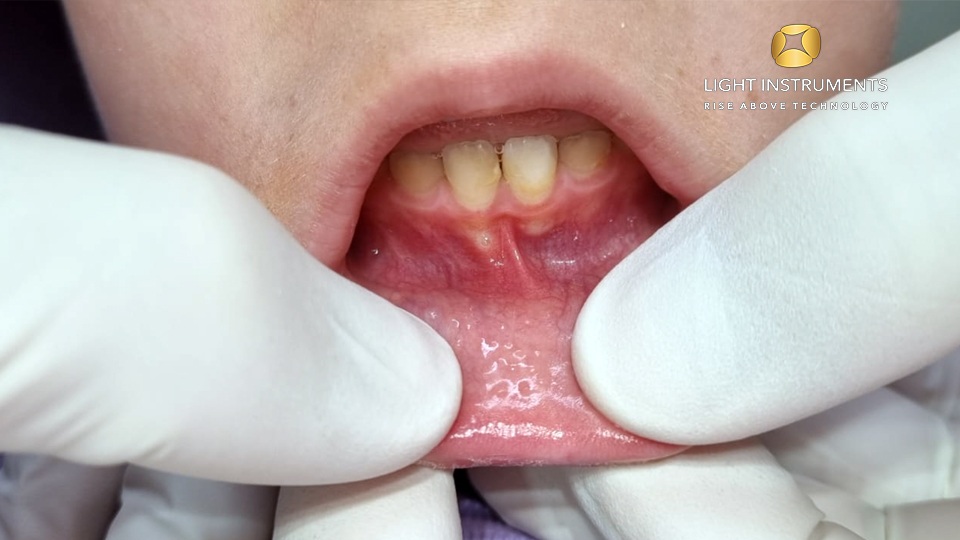

The D-Storm™ Diode Laser is versatile and can be used for various pediatric dental procedures, including frenectomy, frenotomy, gingivectomy, and ulectomy. Its ability to provide hemostasis and promote faster healing makes it an invaluable tool in pediatric dentistry.